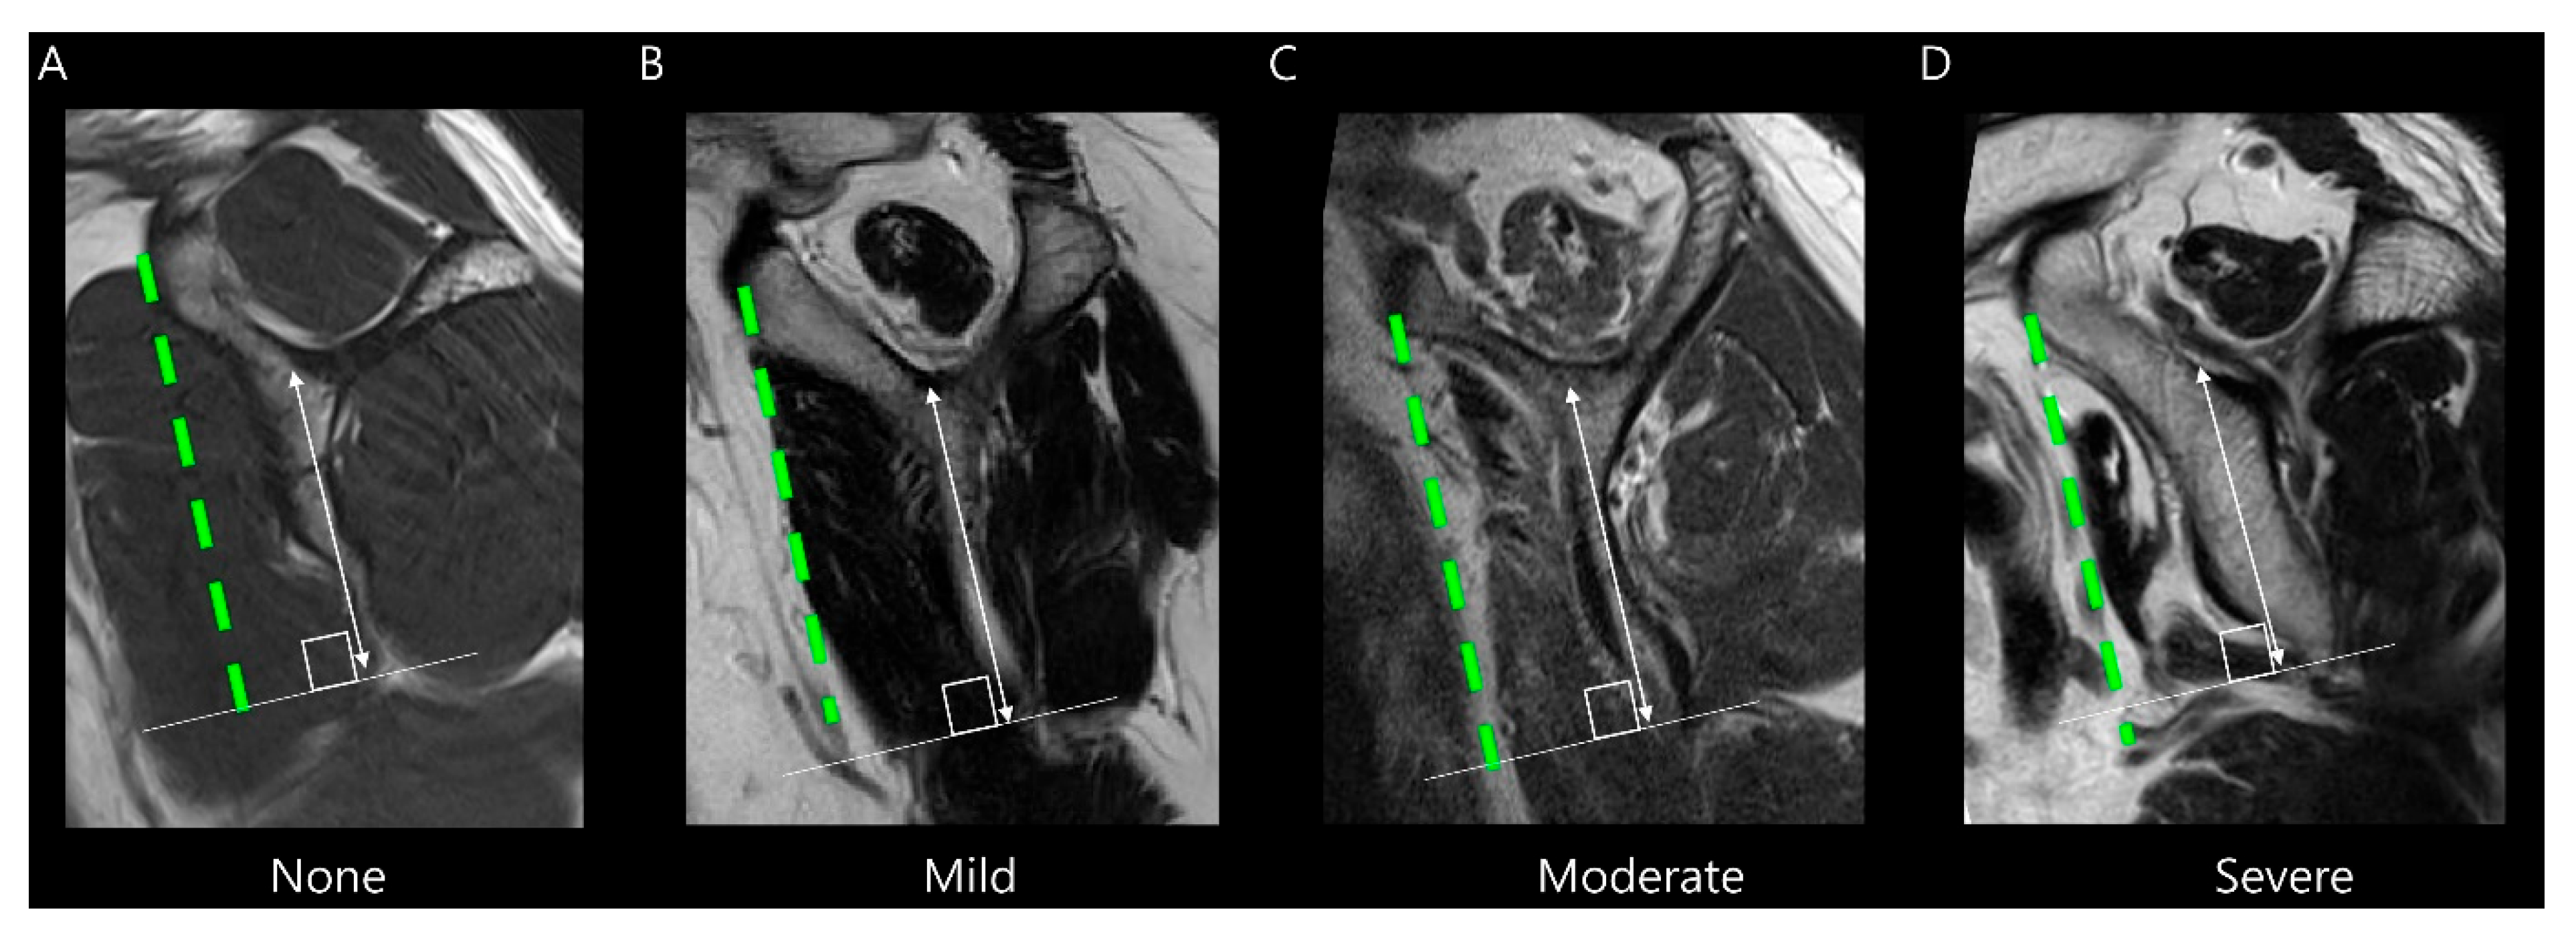

Subscapularis muscle atrophy was evaluated using the Warner classification [12] and the method described by Seppel et al. [13]. The muscle area of the subscapularis was measured in the “Y-position” on the oblique sagittal plane, defined as the most lateral image where the scapular spine contacts the body of the scapula. A virtual reference line was drawn from the superior border of the coracoid process to the inferior margin of the subscapularis muscle at the level of the scapular inferior tip, parallel to the long axis of the scapular body (Figure 4). If the muscle is convex above the line, there is no atrophy. If the muscle contour is even with the line, mild atrophy exists. If the contour of the muscle is concave below the line, moderate atrophy is present. If there is barely any muscle visible, severe atrophy exists [12]. For statistical analysis, we categorized muscle atrophy into two categories: non-mild and moderate–severe degrees.

Figure 4.

Evaluation of subscapularis muscle atrophy on T2-weighted oblique sagittal images. The grade is determined by the amount of muscle above or below a virtual line (green dashed line) drawn from the superior border of the coracoid process to the inferior margin of the subscapularis muscle at the level of the scapular inferior tip (solid line), parallel to the long axis of the scapular body (double-headed arrow). (A) None, (B) Mild atrophy, (C) Moderate atrophy, and (D) Severe atrophy.